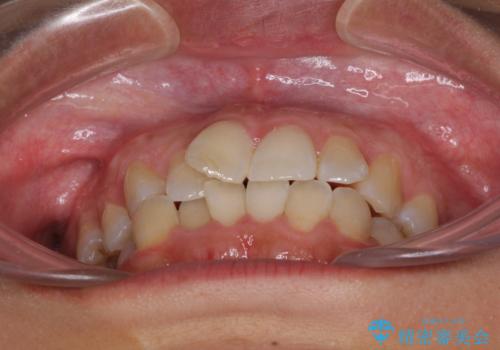

前歯のデコボコをインビザラインでスッキリと仕上げる

- 上下前歯のデコボコと奥歯の銀歯を気にして来院された患者様です。

口元をインビザラインにより歯列を整え、その後に失活している奥歯をオールセラミッククラウンにて補綴治療することとしました。

長時間のマウスピース装着に協力いただき、自然な口元に仕上げることができました。

気になっていた銀歯もオールセラミッククラウンで本物の歯のようになり、患者様には大変満足していただきました。